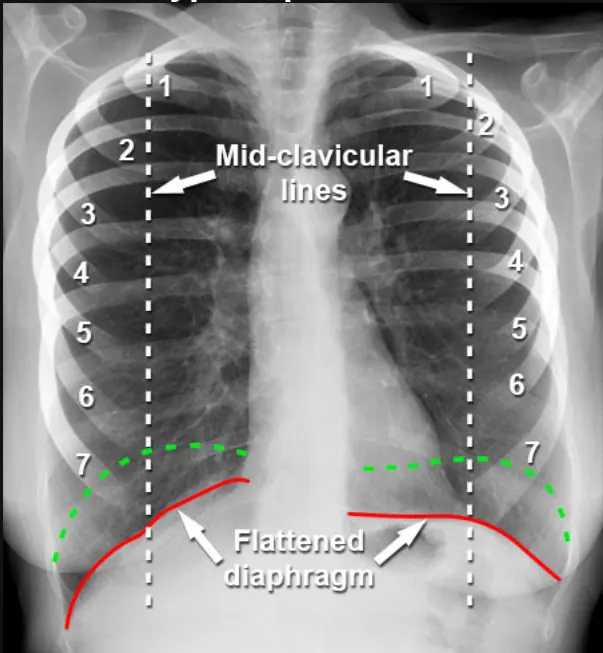

Do the Lungs Look Overly Large?

Lungs that look too big on an X-ray can be a sign of hyperinflation. This is common in people with chronic obstructive pulmonary disease (COPD).

When lungs are chronically overfilled with air, the diaphragm flattens and the chest may appear expanded. You might also see more space between the ribs and fewer visible blood vessels.